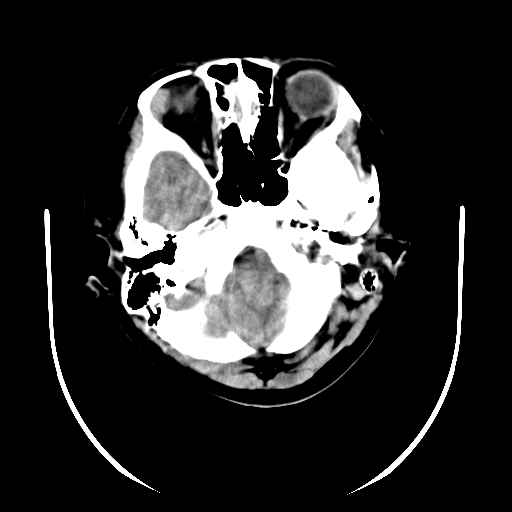

标题: PED3080:女,6岁,头痛、呕吐一天。 [打印本页]

女,6岁,头痛、呕吐一天。

颅脑ct平扫未见明显异常。

头颅ct平扫未见明确异常,随诊复查。